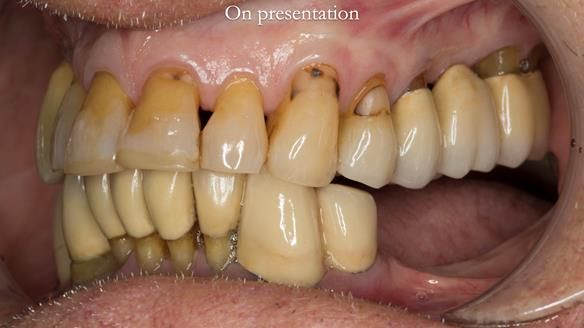

Ken – going downhill, first class

I first met Ken in 2015, when he was 80 years old.

He had lived in both the UK and the USA, spending many years in Florida, where he received extensive dental and periodontal care.

The starting point

We began with the lower jaw.

Final thoughts

This case was always about function, not aesthetics.

Ken’s teeth were never going to look perfect.

There were stained composites, old restorations, and obvious wear.

That was accepted from the outset.